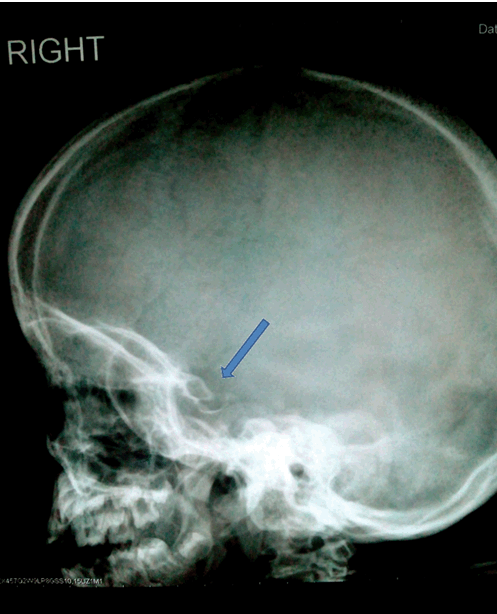

A five-year-old girl was presented at Armed Forces Institute of Radiology and Imaging for skeletal survey. On clinical examination she had corneal clouding, coarse facial features, short stature, and kyphotic deformity of spine. On radiography, skull was enlarged and J shaped sella, spine showed increased curvature and anterior beaking of vertebra. X-ray chest showed anterior widening of ribs (oar shaped ribs). Pelvis had widely flared iliac bones. Hand X-ray revealed proximal pointing of metacarpals of both hands. There was no mental retardation. She was diagnosed with mucopolysaccharidosis type IV: Morquio syndrome.

Figure 2: Arrow showing J-shaped Sella.